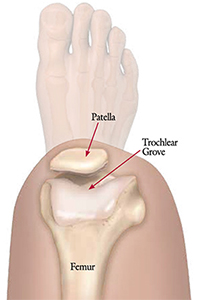

The patella has several functions in the human body including assisting in quadriceps extension by increasing the lever arm of the patellar tendon, centralizing the multi-directional forces transmitted from the four muscles of the quadriceps, distributing tension from the femur to the patellar tendon and protecting the tibiofemoral joint anteriorly [1]. During flexion and extension the patella articulates with the trochlea on the anterodistal end of the femur to form the patellofemoral joint. The trochlea is composed of a medial and lateral facet separated by a central groove that deviates laterally from the axis of the femoral shaft and deepens in depth distally. The sulcus angle measures the depth of the groove and averages 138° ± 6°. Between 0° and 40° of extension, the patella engages with the lateral facet of the trochlea and this engagement stabilizes the patella against the lateral pull of the quadriceps. Conversely, during flexion, the patella moves medially from 0° to 20°; beyond 20° of flexion, the patella catches and engages with the trochlea and then moves medially until 90° of flexion [2, 3].

Because the patella engages with the trochlear groove in both flexion and extension, any alteration in trochlear anatomy can greatly influence the biomechanics and stability of the patellofemoral joint. A dysplastic trochlea is quantitatively defined as a sulcus angle >145°. This increased sulcus angle presents as a flattened, more shallow trochlear groove and can be a result of variations in facet height and/or groove depth; such trochlear variations can affect the relative measurements of associated anatomic landmarks, including the tibial tuberosity to trochlear groove (TT-TG) distance, the height of the patella and the lie of the patella, including patellar shift or tilt [2, 4]. Furthermore, these anatomic alterations can influence the integrity of surrounding soft-tissue structures like the medial patellofemoral ligament (MPFL), medial patellotibial ligament and the vastus medialis obliquus muscle (VMO). All of the aforementioned factors, when compromised or altered, can lead to recurrent episodes of atraumatic patellofemoral instability which the patient perceives as 'giving way' or 'popping out' or 'dislocating'.